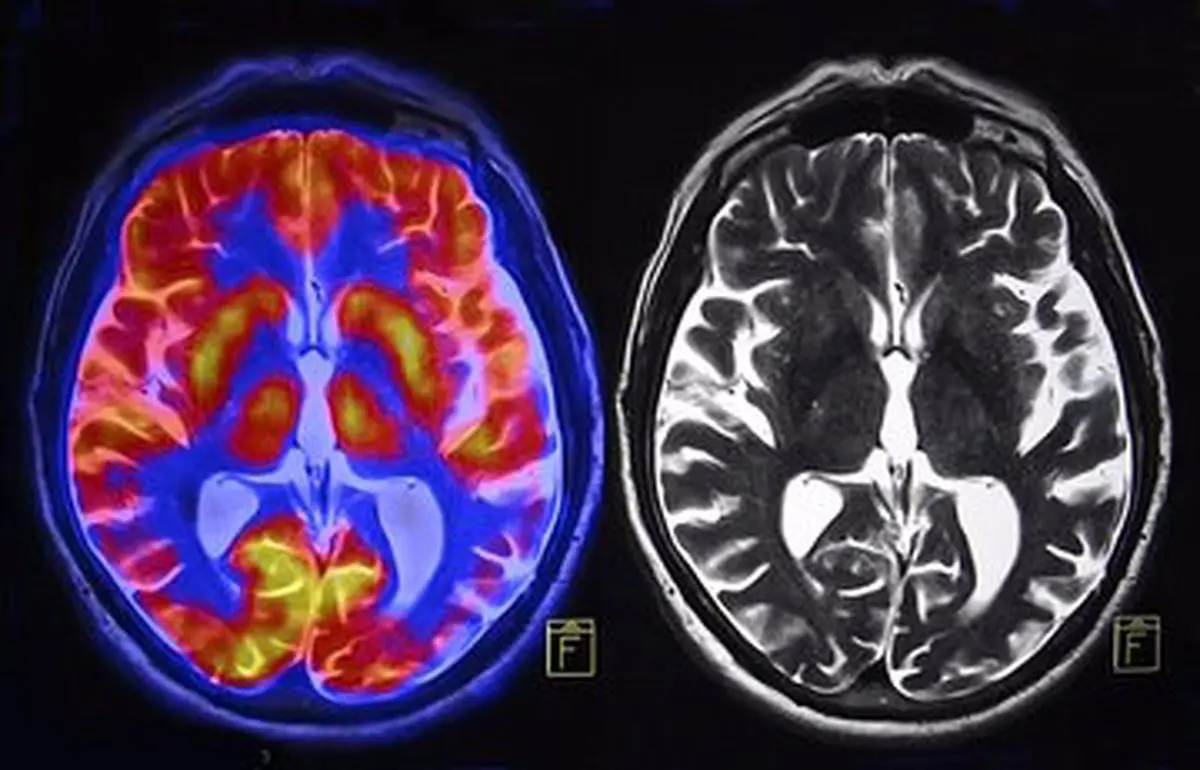

مغز زن و مرد چقدر فرق دارند؟

دانشمندان با ابداع یک مدل هوش مصنوعی با دقت بیش از ۹۰ درصد، به بررسی تفاوت اسکنهای فعالیت مغز زنان و مردان پرداختند.